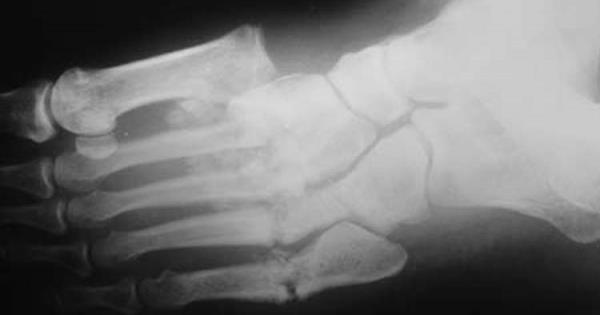

Para confirmar el padecimiento los médicos pueden utilizar una radiografía para detectar la presencia de una posible lesión articular, también pueden ayudarse de la ecografía y la gammagrafía. Además entre más pronto se detecte la enfermedad, los médicos podrán cambiar el curso de la enfermedad.